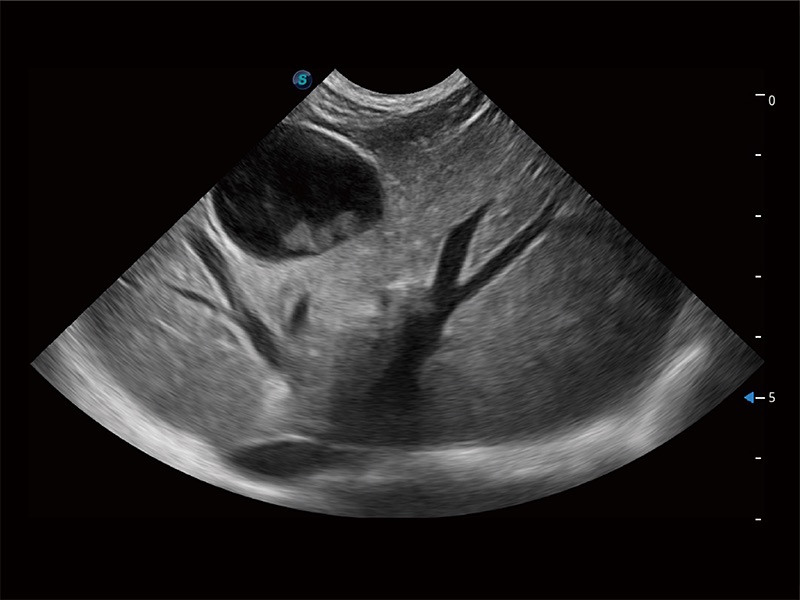

ProPet 80 配备了丰富的心脏探头群、先进的成像技术和专业的心脏测量工具,可帮助动物医生为不同体型和生理结构的动物提供心脏和心肌功能的全面评估。

实时用颜色表示心肌组织运动,观察和定量组织的运动情況,对快速检测与评估心肌的灌注和活性、电传导及心肌收缩和舒张功能等均能提供重要的诊断信息。

通过心肌识别技术与二维斑点追踪技术相结合,对心脏的超声图像进行量化分析。计算心肌17个节段的应变、应变率、速度、位移等,并通过牛眼图的形式进行呈现。

通过360度任意调节3条M型取样线,在同一心动周期上观察心脏不同位置的运动曲线,得到准确的心功能测量数据,有效评估心肌运动及左心室功能。

能够基于左心室壁追踪和辛普森法,自动计算射血分数,支持多个可移动点描迹,与手动测量相比,极大节省了动物医生的时间和精力。